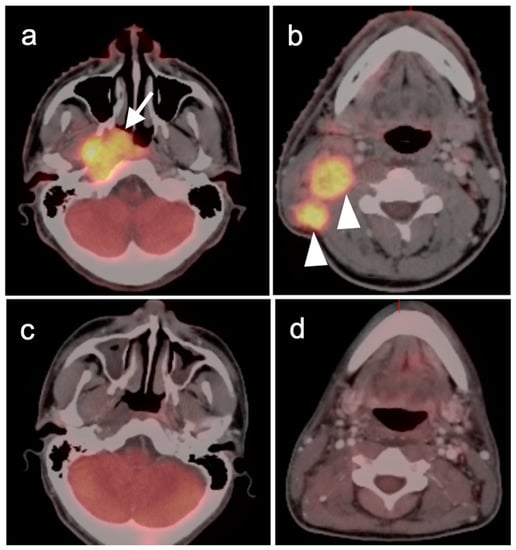

2.3. Nasopharyngeal Carcinoma

2.4. Sinonasal Tumors